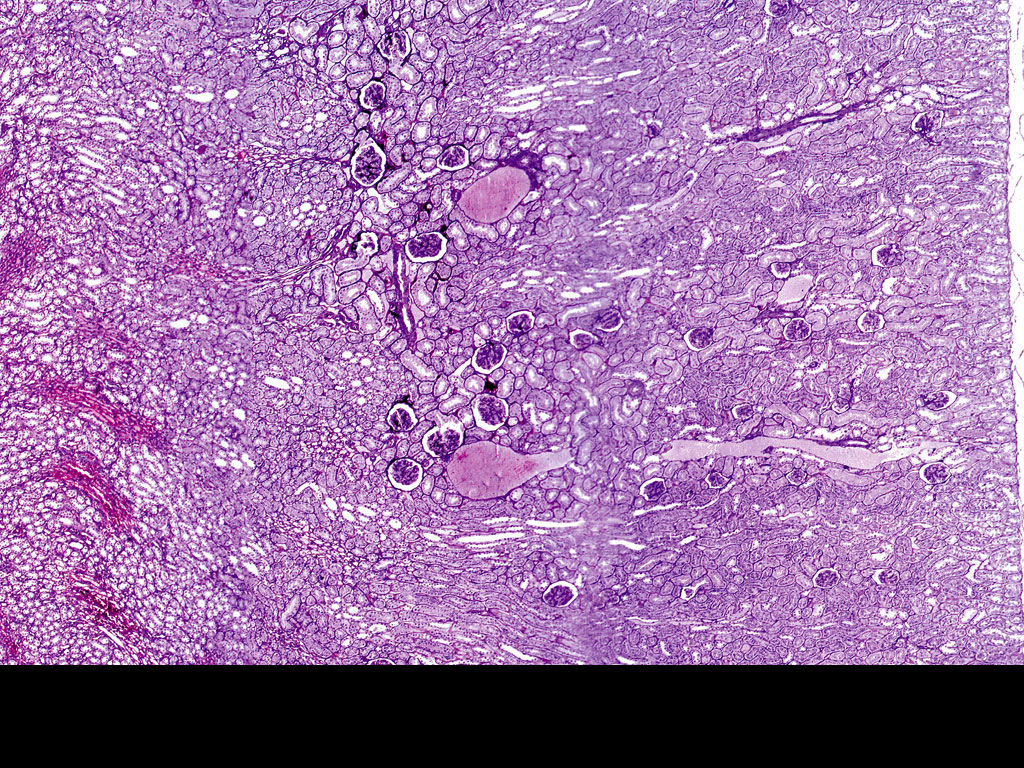

Distinguishing Features on Slide

- Renal corpuscles (glomerulus within Bowman's capsule) visible as round structures in cortex

- PCT with brush border and columnar cells โ most prominent tubular profile

- DCT with cuboidal cells and no brush border โ simpler epithelium

- Loop of Henle thin segments in medulla โ lined by squamous cells

- Collecting ducts with cuboidal cells, very clear cell boundaries

- Rich blood vessel supply including afferent and efferent arterioles